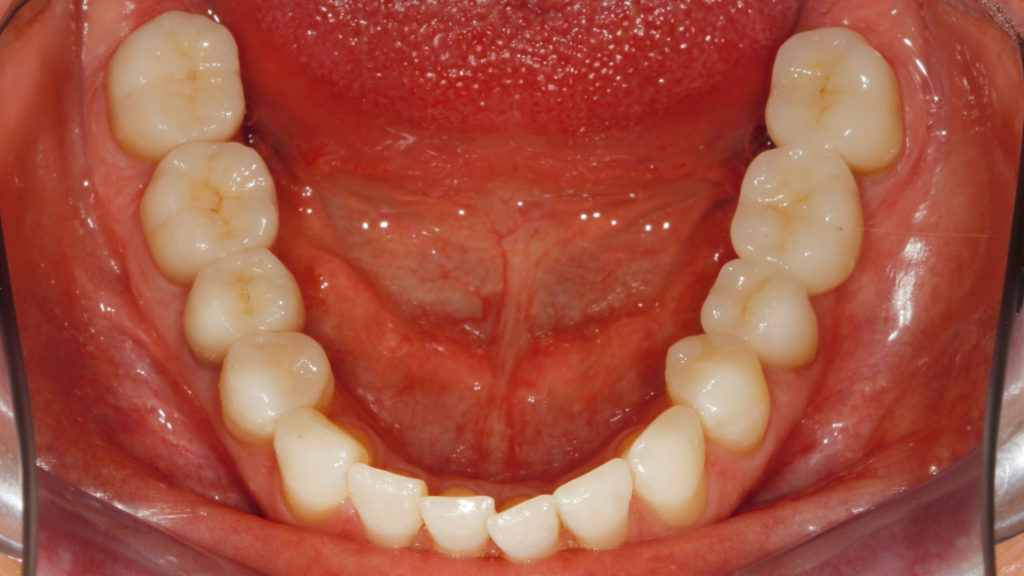

Bei der Patientin wurde über eine funktionelle Initialtherapie die neue vertikale Bisshöhe mittels Schiene über einen Zeitraum von sechs Monaten etabliert (Abb. 4). Für den Aufbau der Zähne zum dauerhaften Stabilisieren der VDO waren keramische Restaurationen geplant. Im ersten prothetischen Therapieschritt sollten die Zähne im Oberkiefer versorgt werden. Dafür wurden alle Zähne präpariert, wobei ein substanzschonendes Vorgehen im Fokus stand. Im Seitenzahngebiet sollten eine Brücke (25 auf 27) und ansonsten Einzelkronen gefertigt werden. Die Oberkiefer-Frontzähne wurden für die Aufnahme von 360°-Veneers präpariert, da aufgrund der Bisshebung auch die palatinalen Bereiche in die Restauration eingebunden werden mussten. Um die validierte Bisshöhe zu stabilisieren, erhielt die Patientin nach der Präparation im Oberkiefer beziehungsweise dem Einsetzen der provisorischen Versorgung die Schiene im Unterkiefer wieder eingegliedert. Im Labor wurden vollkeramische Restaurationen aus Lithiumdisilikat angefertigt und zugleich die noch nicht präparierten Zähne im Unterkiefer additiv aufgebaut. Es wurde eine Art „Deckel“ aus Komposit in entsprechender Morphologie und Bisshöhe angefertigt. Unmittelbar nach der adhäsiven Eingliederung der keramischen Restaurationen im Oberkiefer konnten diese temporären Versorgungen ohne Präparation auf den unteren Zähnen befestigt werden. Die Patientin erhielt so die Möglichkeit, die Situation – die neue VDO – nochmals zu testen, nun bereits mit neu versorgtem Oberkiefer. Im zweiten prothetischen Therapieschritt wurden die Zähne im Unterkiefer präpariert. Im Frontzahnbereich (Zähne 34 bis 44) kam der Pfullinger Wellenschliff zur Anwendung (Abb. 5). Die Vorteile dieser Präparationsart in diesem Fall waren die geringe Invasivität, das vereinfachte Handling bei der Herstellung der Frontzahnveneers sowie deren Eingliederung. Aufgrund des reduzierten Präparationsdesigns musste nur in den vestibulären Bereichen Substanz abgetragen werden. Der Wellenschliff erfordert Fingerspitzengefühl und Präzision – ein geringer zeitlicher Mehraufwand, der sich jedoch aufgrund der Vorteile, die diese Präparationsart mit sich bringt, lohnt. Im Seitenzahnbereich wurden die Zähne für die Aufnahme einer Brücke von Zahn 45 auf Zahn 47 sowie für Kronen und Teilkronen von 35 bis 37 vorbereitet. Nach einer Überabformung (Abb. 6) wurde die Grundzahnfarbe als Basis für die Rohlingauswahl bestimmt (Abb. 7).

Auch dieser Patient hatte eine stark abgesenkte vertikale Bisshöhe (Abb. 26). Mit einer funktionalen Initialtherapie mittels Schiene im Unterkiefer wurde eine neue Bisshöhe validiert. Nach Akzeptanz der Bisslage erfolgte die prothetische Rehabilitation, wobei erneut in zwei Phasen vorgegangen wurde. Die während der Initialphase erarbeitete Bisslage sollte mit keramischen Restaurationen dauerhaft stabilisiert werden. Im Oberkiefer sollten dafür die Zähne 15 bis 17 mit einer Brücke, 14 mit einer Krone und 24 mit einer Teilkrone versorgt werden. Für die Frontzähne waren 360°-Veneers geplant, um auch die Palatinalflächen aufbauen zu können.

Grundsätzlich ist es bei einer solchen Therapie unverzichtbar, während der prothetischen Phase die neue Bisshöhe zu erhalten. Daher wurde wie im ersten dargestellten Fall zunächst der Oberkiefer präpariert, mit Provisorien versorgt und im Unterkiefer die Schiene wieder eingegliedert. Nach der therapeutischen Phase wurden im Labor die vollkeramischen Restaurationen hergestellt. Während im vorangegangenen Fall indirekte temporäre Kompositrestaurationen („Deckel“) für die Unterkiefer-Frontzähne im Labor erstellt worden waren, kam in diesem Fall – aufgrund des vergleichsweise geringen Platzangebots – die direkte Methode zur Anwendung. Nach dem Einsetzen der vollkeramischen Restaurationen im Oberkiefer diente ein im Labor auf der Basis eines Wax-ups hergestellter Silikonschlüssel (transparentes Formteil) dem Herstellen temporärer Chairside-Restaurationen aus lichthärtendem Komposit. Der Patient testete in den folgenden Wochen die Situation und die neue Bisslage. Danach erfolgte die Präparation der Zähne im Unterkiefer. Die Zähne 46, 47, 35, 36 (Implantat), 37, 38 wurden für die Aufnahme von Kronen und 44/34 sowie 45 für Teilkronen (mit vestibulärem Wellenschliff) vorbereitet und die Frontzähne im Sinne eines optimalen Substanzerhalts nach dem „Pfullinger Wellenschliff“ präpariert (Abb. 27). Zahn 41 hatte bereits eine Krone, weshalb dort die Präparation nur leicht angepasst worden ist. Bei diesem Fall wurde ein reduzierter Wellenschliff vorgenommen. Das Herstellen der keramischen Restaurationen sowie die adhäsive Eingliederung folgten dem im Fall 1 beschriebenen Vorgehen (Abb. 28 bis 34). Erneut spielte der Wellenschliff seine Vorteile aus: vereinfachtes Handling in Praxis und Labor, geringe Invasivität sowie aufgrund des unregelmäßig verlaufenden Präparationsrands diffuser, augenscheinlich nicht sichtbarer Übergang zwischen Zahn und Keramik.